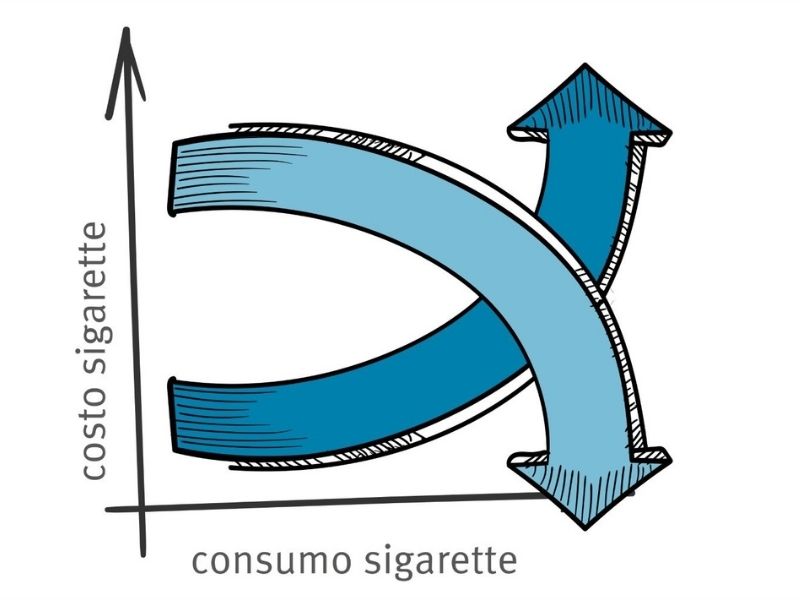

Il ruolo del fumo e le conseguenze evitabili

Il principale fattore di rischio è il fumo, per il quale è chiara la relazione dose-effetto. La relazione tra esposizione e rischio di malattia è diretta: più a lungo e più intensamente si fuma, maggiori sono i danni. In Italia, il fumo provoca circa 93.000 morti ogni anno, legate non solo al tumore del polmone, ma anche a quello del cavo orale, e a gravi patologie cardiovascolari e respiratorie.